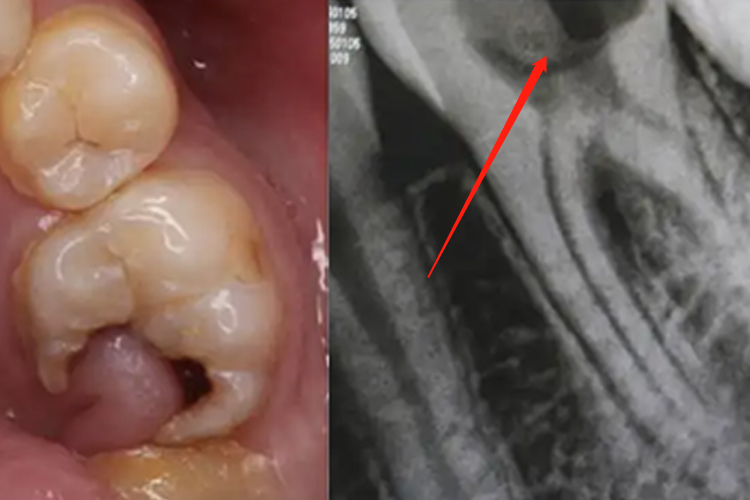

牙龈息肉在临床上一般采取牙龈息肉切除术,即自蒂部将息肉切除,以达到较好的预后。若局部已经有明显炎症,需遵医嘱使用抗生素治疗,如头孢美唑、甲硝唑等。若突然破损出血严重,需咬合干净的棉球进行压迫止血。

同时需积极治疗龋病,可磨除已经龋坏的部分后进行填充修补。若伴随根尖周炎,需进行根管治疗。若牙体龋坏严重,可进行牙冠修复。